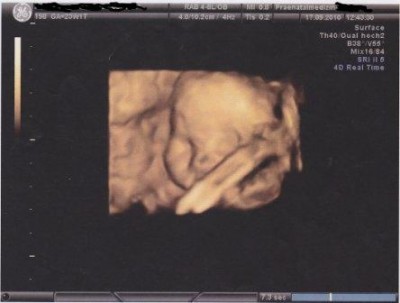

@me wurde letztes Wochenende mit Babysachen überhäuft. Heute hatte ich wieder einen Hebi-Termin. Habe mich jetzt für einen GVK sowie Schwangerschafts-Yoga angemeldet. Freue mich schon drauf. Ansonsten geht es mir und Krümelchen sehr gut.